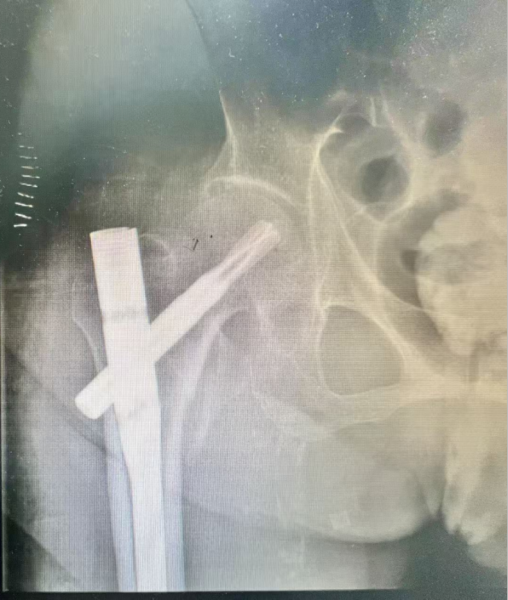

图3:术后骨盆正位片,骨折对位对线良好,恢复了阳性支撑,颈干角恢复,纠正了髋内翻畸形。

经过周密的术前准备,在患者入院24小时内,一场与时间赛跑、与风险博弈的微创手术正式启动。麻醉科马鸿雁主任医师、魏邵婷主治医师为这位百岁老人选取了损伤最小、疼痛程度最低的先神经阻滞再腰麻的方式进行麻醉,麻醉成功后,程道林主治医师在王岩松主任的全程指导、手术室刘博护士的密切配合及麻醉科等相关科室的保驾护航下,精准实施右侧股骨转子间骨折闭合复位髓内钉固定微创手术。整个过程顺利、精准、高效,仅用时15分钟便完成骨折复位与有效固定,术中出血少、创伤极小,最大限度降低了手术对百岁老人身体的刺激,践行了“微创治疗、快速康复”的诊疗原则。

术后护理阶段,科室医疗团队与高磊护士长带领的护理团队密切配合,为老人制定了个性化康复计划,全程监测生命体征,精准调控用药,耐心指导康复训练。令人欣喜的是,术后第二天,老人就在家属的辅助下成功下床进行功能锻炼,精神状态稳步好转,不仅有效规避了卧床引发的各类致命并发症,更极大地保留了生活自理能力,改善了晚年生活质量,用专业实力打破了“百岁老人骨折难康复”的魔咒,并在年前顺利出院与家人团聚。